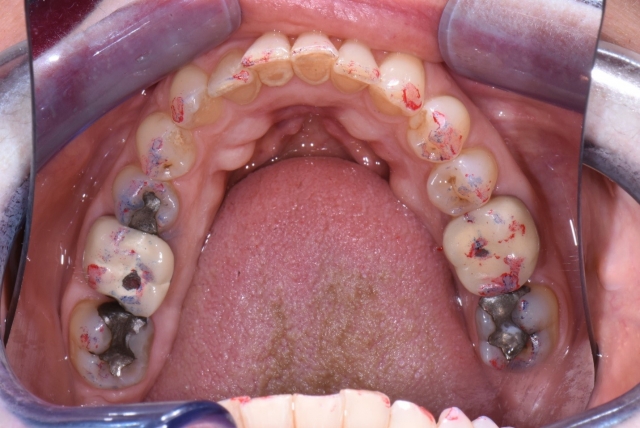

I use photography to share what I see with my patients. We document occlusion using photos with articulating paper.

It is now easy to share with a patient that in a “good bite,” I would like to see blue dots on the back teeth and red stripes on the front teeth. I then point out how the very colorful teeth had a part to play in their dental breakdown. I also point out other areas that concern me and, if left alone, may have similar consequences.